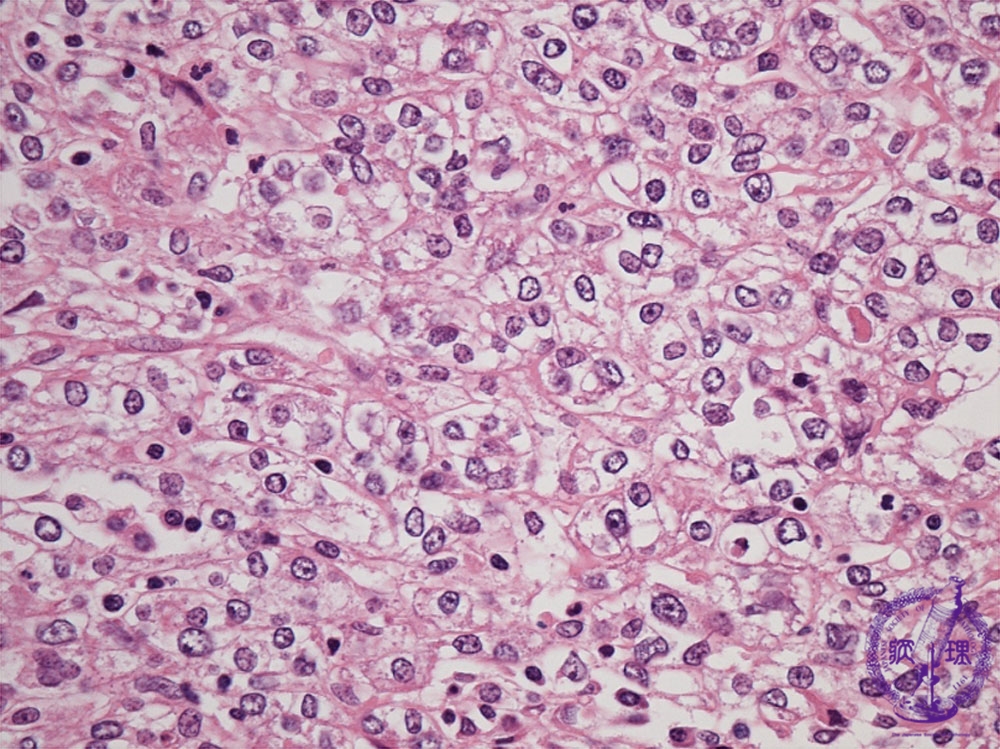

Histology (HE stain, high power): Carcinoma cells with clear cytoplasm grew/formed(?) in a solid structure.